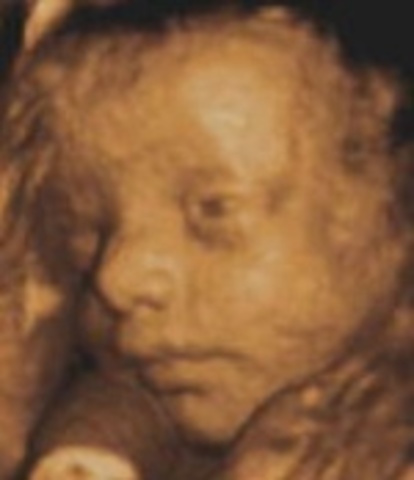

• Week Twenty Seven: Eyes can open

Week Twenty Seven: Eyes can open

Your baby's hearing continues to develop. The eyes can blink, open and close.